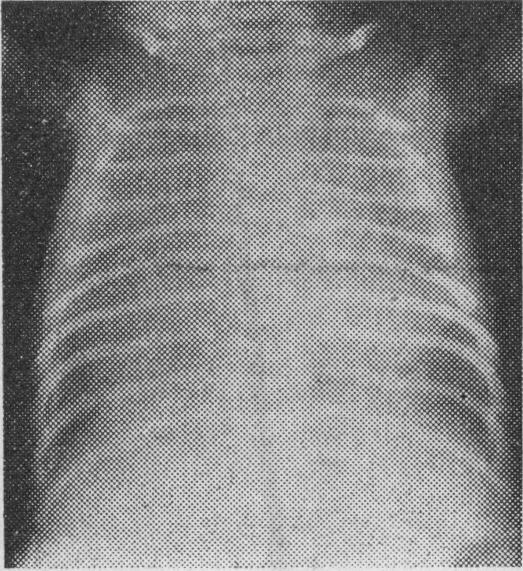

Infracardiac total anomalous pulmonary venous drainage.

Infracardiac total anomalous pulmonary venous return (TAPVR).

Infracardiac total anomalous pulmonary venous drainage: a diagnostic challenge.

Total anomalous pulmonary venous return below the diaphragm.

Infradiaphragmatic total anomalous pulmonary venous connection.